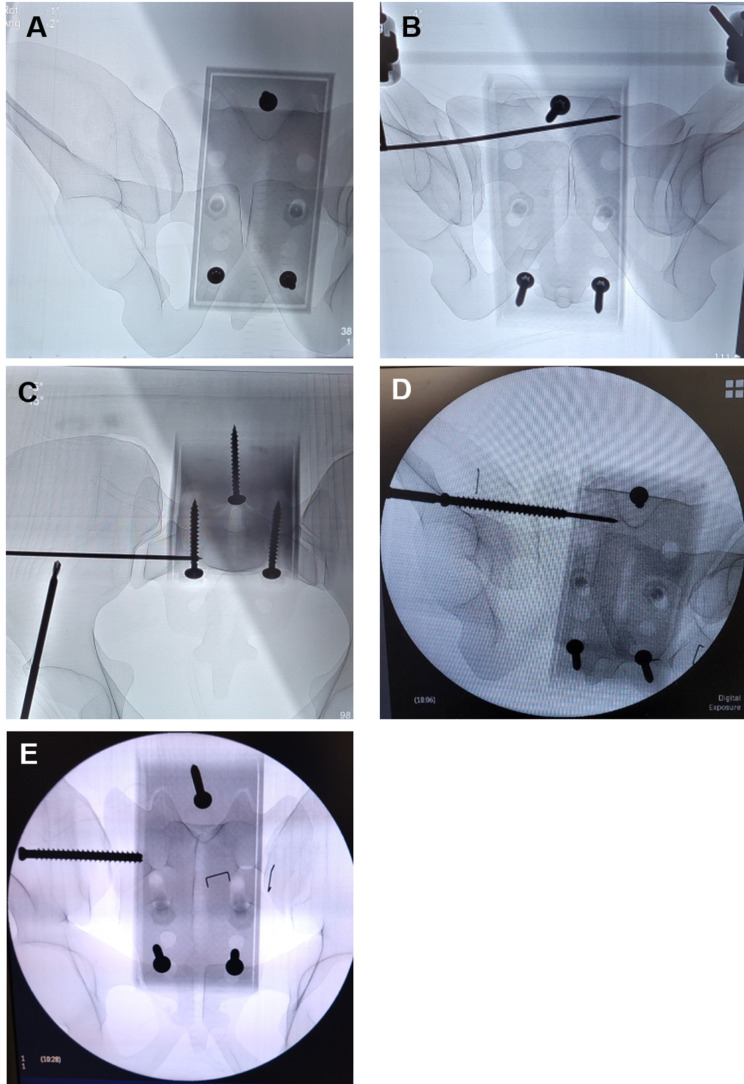

Methods: A standardized simulator of an unstable pelvic ring utilizing synthetic pelvic bones featuring complete disruption of the symphysis and sacroiliac joint was developed. Trauma surgeons of a level one academic hospital were invited to perform external fixation and emergency sacroiliac screw application under C-arm guidance. Prior to and following the simulation session, participants completed a subjective questionnaire assessing their confidence in emergency interventions on a 10-point Likert scale (10-LS). Objective parameters, such as intraoperative imaging quality, reduction accuracy, and the positioning of screws, wires, and external fixators, were also evaluated as secondary outcome measures.

Results: Fifteen trauma surgeons (10 residents, 5 consultants) participated in the simulation over the course of one day. The mean total operation time was 20.34 ± 6.06 min, without significant differences between consultants and residents (p = 0.604). The confidence for emergency SI-Screw placement increased significantly after the simulator (10-LS: Before = 3.8 ± 3.08 vs. After = 5.67 ± 2.35; p = 0.002) as well as after external fixation (10-LS: Before = 3.93 ± 2.79 vs. After = 6.07 ± 2.52; p = 0.002). In addition, confidence in (intraoperative) pelvic imaging increased significantly (10-LS: Before = 4.60 ± 3.0 vs. After = 6.53 ± 2.39; p = 0.011). Overall, the model was rated as a realistic simulation of clinical practice (10-LS = 7.87 ± 1.13).